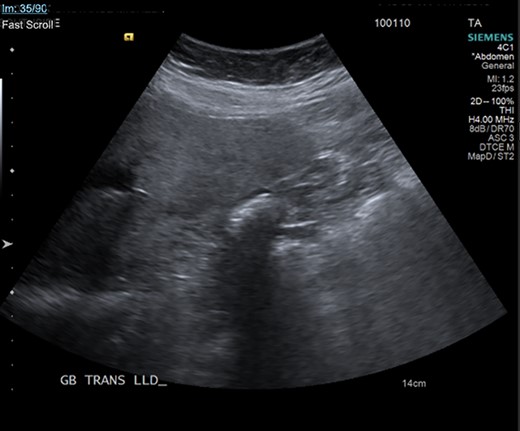

At her initial presentation in the emergency department, the patient underwent an abdominal ultrasound, which showed a collapsed gallbladder around gallstones. Due to this finding, she was referred to the surgery clinic. After further discussion with the patient at the clinic, her symptomology was more characteristic of colonic spasm for which she was prescribed hycosamine. A hepatobiliary iminodiacetic acid (HIDA) scan was ordered for further investigation, but she failed to follow up.

Gallbladder agenesis is a rare anomaly in which an individual is born without a gallbladder. This phenomenon affects <0.1% of the population with only 400 cases documented in medical literature to this day [2, 3]. This anomaly is discovered incidentally during workups for symptoms consisting of gallbladder pathology as seen in our patient. Initial work up for a gallbladder pathology includes a right upper quadrant ultrasound and, in this patient, it showed a collapsed gallbladder around gallstones, as seen in Fig. 4. This pointed to a diagnosis of cholecystitis. A further look with a HIDA scan confirmed this diagnosis as it showed the absence of radiotracer entering the gallbladder even after the administration of morphine, seen in Figs 5 and 6. A non-visualized gallbladder typically occurs due a gallstone obstructing the passage of the radiotracer entering the gallbladder [4]. Gallbladder agenesis could cause this radiographic finding as well, however, this anomaly was low in our differential as the initial ultrasound showed a collapsed gallbladder and the patient’s absence of other medical conditions associated with gallbladder agenesis, such as Klippel–Feil syndrome, horseshoe kidney, malrotation of the gut or aberrant left pulmonary artery, none of which were suspected in our patient seen on examination and radiographically [1]. The normal location of the gallbladder is located on the undersurface of the liver, aligning with the intrahepatic line that separates the right and left hepatic lobe. There was no sign of this organ once the liver was elevated, seen in Fig. 1. The likely cause of this patient’s chronic right sided abdominal pain were the multiple abdominal adhesions, which were lysed.

Ultrasound of the gallbladder showing echogenic shadow from the gallbladder fossa around gallstones, suggesting a collapsed gallbladder around stones.